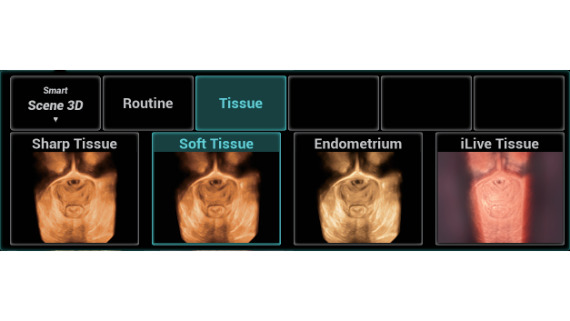

El sistema Nuewa I9, dise?ado exclusivamente para la atenciĂłn mĂ©dica neonatal y de mujeres, brinda una experiencia innovadora integral. Estas innovaciones se desarrollan sobre la base de un conocimiento profundo de situaciones clĂnicas complejas para proporcionar respuestas precisas y oportunas, una gran eficiencia y una experiencia de usuario extraordinaria.

La plataforma ZST+?es una innovaciĂłn extraordinaria que representa toda una evoluciĂłn en el ĂĄmbito de la ecografĂa. Transforma las mĂ©tricas ecogrĂĄficas de la formaciĂłn de haces convencional al procesamiento basado en datos de canal. Supera la limitaciĂłn tradicional de tener que equilibrar entre resoluciĂłn espacial, resoluciĂłn temporal y uniformidad del tejido, con lo que ofrece una calidad de imagen excepcional para soluciones de producciĂłn de imĂĄgenes infinitas con mejoras continuas.